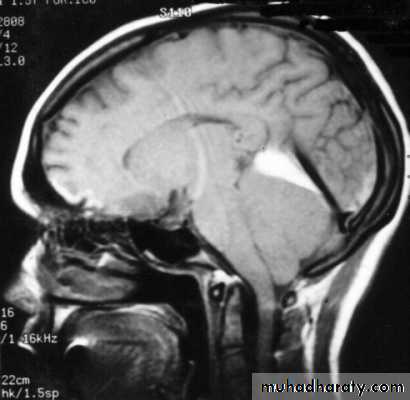

1. Brain Oedema (Cerebral Swelling)

Can be local (around a haematoma) or diffuse.

It is due to intracellular or extracellular accumulation of fluid.

It leads to raised intracranial pressure, which itself causes problems.

It is more common and more dangerous in children.